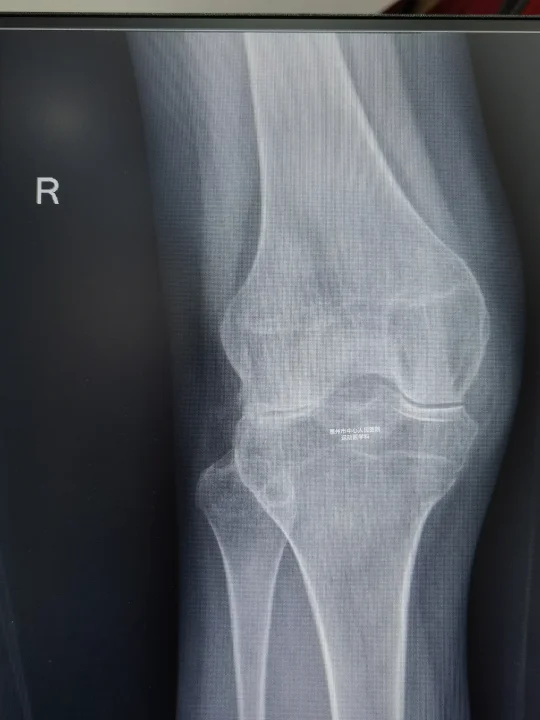

门诊病例 71岁女性,突发右膝疼痛2个月,走路都非常困难。 第...